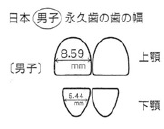

■歯の大きさ

| 場所(部位) | 本人の歯幅径(mm) | 日本人の平均男性 | 差(+・-)mm |

|---|---|---|---|

| 上顎中切歯 | 右側 9.4 左側 9.1 |

8,59mm | +0.81 +0.51 |

| 下顎中・側切歯 | (右側) 中切歯 5.8 側切歯 7.0 (左側) 中切歯 6.0 側切歯 6.9 |

5,44mm |

(右側) +0.36 +1.56 (左側) +0.56 +1.46 |